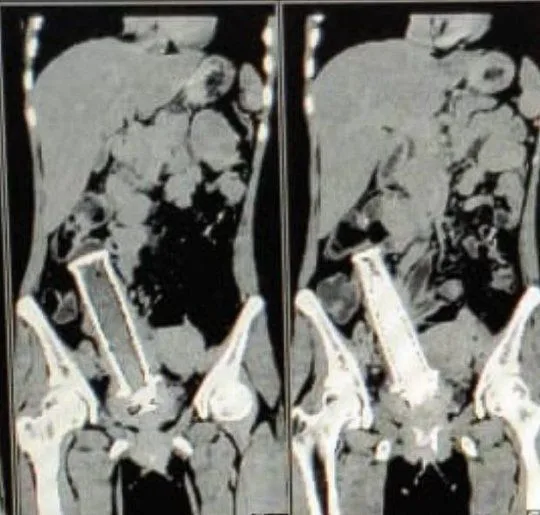

ทีมแพทย์ 19 คน ต้องใช้เวลานานกว่า 4 ชั่วโมง ในการนำการแฮนด์รถจักรยานยนต์ออกมาจากช่องคลอดของเธอ

แฮนด์รถจักรยานยนต์ ถูกสอดเข้าไปผ่านช่องคลอด

รองศาสตราจารย์ ดร. โซเนีย โมเสส เปิดเผยเบื้องหลังเหตุการณ์ที่น่าตกใจว่า ผู้ป่วยเผยว่า เธอถูกสามีที่เมาเหล้าใช้แฮนด์รถจักรยานยนต์สอดเข้าไปช่องคลอดของเธอตั้งแต่สองปีก่อน

ต้องใช้เเพทย์ถึง 19 คน และใช้เวลาผ่าตัดถึง 4 ชั่วโมง ในการรักษาผู้ป่วย

สามียังขู่เธอให้ปิดเรื่องนี้เป็นความลับ จนเธอมีอาการปวดท้อง เนื่องจากอาการติดเชื้ออย่างรุนแรง ทำให้แพทย์ต้องตัดมดลูกออกมาเพื่อช่วยชีวิต และเธอไม่สามารถมีลูกได้อีกต่อไป